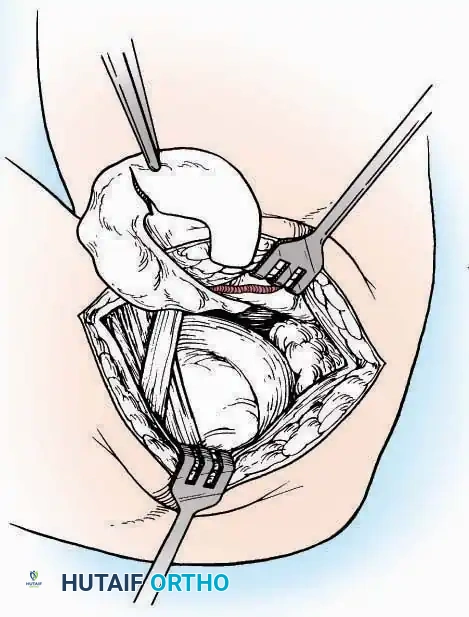

Medial Approach

Indications: Fixation of sustentaculum tali fractures, medial process fractures, or excision of medial tarsal coalitions.

Positioning: Supine with the hip externally rotated and knee flexed (figure-of-four position).

Surgical Technique:

* Incision: Begin 2.5 cm anterior and 4 cm inferior to the medial malleolus. Carry it posteriorly along the medial surface of the foot toward the Achilles tendon.

* Superficial Dissection: Divide the fat and fascia to define the inferior margin of the abductor hallucis muscle.

* Deep Dissection: Mobilize the abductor hallucis muscle belly and retract it dorsally to expose the medial and inferomedial aspects of the calcaneal body.

* Plantar Exposure: Continue distally by dividing the plantar aponeurosis and the muscular attachments to the calcaneus, or strip them subperiosteally with an osteotome.

* Neurovascular Warning: Meticulously identify and protect the medial calcaneal nerve and the nerve to the abductor digiti minimi (first branch of the lateral plantar nerve), which are highly vulnerable during inferior retraction.